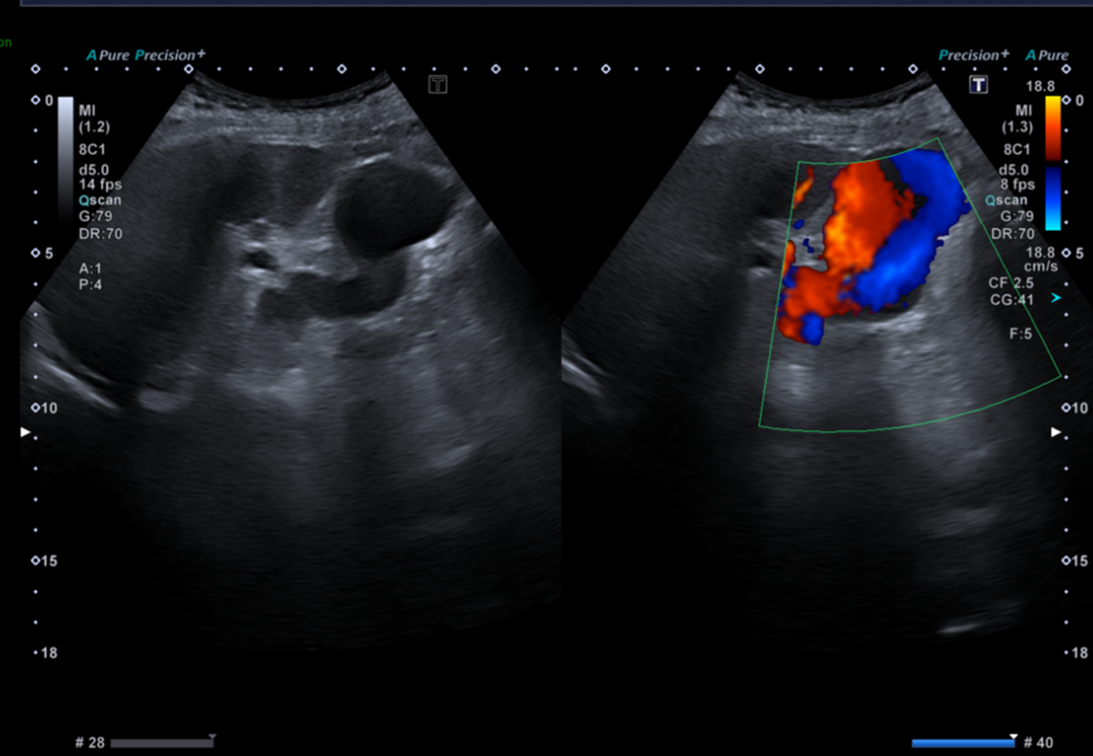

Celui qui aura balayé entièrement l’organe et son environnement, et qui aura complété son examen par le doppler couleur répondra différemment.

Voici le résumé des balayages et réglages réalisés par le manipulateur en échographie.

Ces nouvelles coupes (faisant apparaitre la rate, le doppler couleur et le doppler pulsé), montrent alors non pas un kyste rénal mais des volumineuses veines péri spléniques correspondant à des voies de dérivations spléno-rénales témoignant d’une hypertension portale probablement liée à la cirrhose sous-jacente.